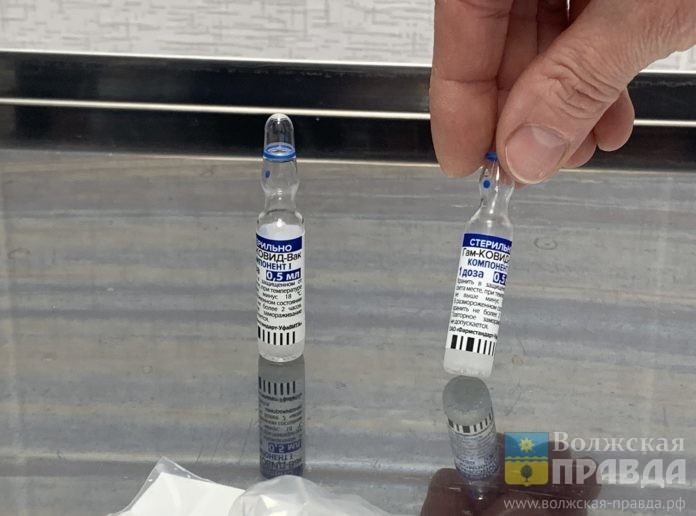

Новую партию — 29160 комплектов препарата «ГамКовидВак» — распределят в прививочные центры региона.

По информации областного комитета здравоохранения, с начала прививочной кампании в Волгоградскую область всего поступил 267 131 комплект вакцины от новой коронавирусной инфекции, в том числе 6 170 препарата «ЭпиВакКорона».